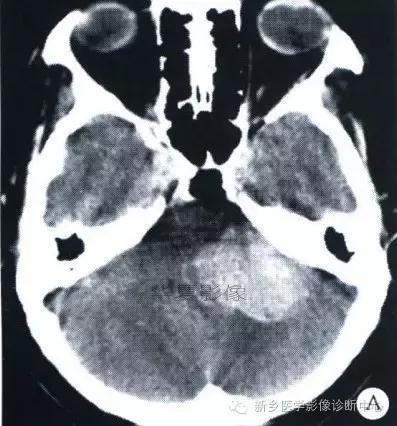

中枢神经系统内原发性黑色素瘤少见, 因脑和脊髓的软脑( 脊) 膜及蛛网膜上含有黑色素细胞, 黑色素可发生于软脑( 脊) 膜的任何部位,故其发生部位常位于脑( 脊髓) 表面, 沿软脑膜生长; 而继发性黑色素瘤同一般转移性肿瘤, 常位于灰白质交界区。

影像表现:常表现为短 T1 高信号, 短T2WI 低信号,又因为黑色素瘤是富血管性肿瘤, 增强扫描常表现为明显强化。

★但少数肿瘤也不具备上述典型信号特征,主要原因是肿瘤内黑色素量多少影响。只有当黑色素瘤中黑色素细胞超过一定含量( ﹥ 10% ) 时, 才会出现黑色素瘤的典型MRI表现; 不典型的黑色素瘤因其黑色素含量较少,不足以缩短T1、T2弛豫时间,而表现为长T1低信号、长T2高信号。

依据黑色素瘤的不同 MRI 影像表现将其分为 4 种类型: ( 1) 黑色素型。该黑色素瘤因含有丰富的黑色素颗粒, MRI表现较典型,即短 T1 高信号,短 T2 低信号。( 2) 无黑色素型。因该类黑色素瘤不含黑色素颗粒或含量较低,MRI 表现为长 T1 低信号,长 T2 高信号; ( 3) 混合型。黑色素型和非黑色素型两者的混合; ( 4) 出血型。表现为血肿不同时期的信号特征, 该黑色素瘤 MRI增强扫描表现为不均匀环状或弥漫性强化